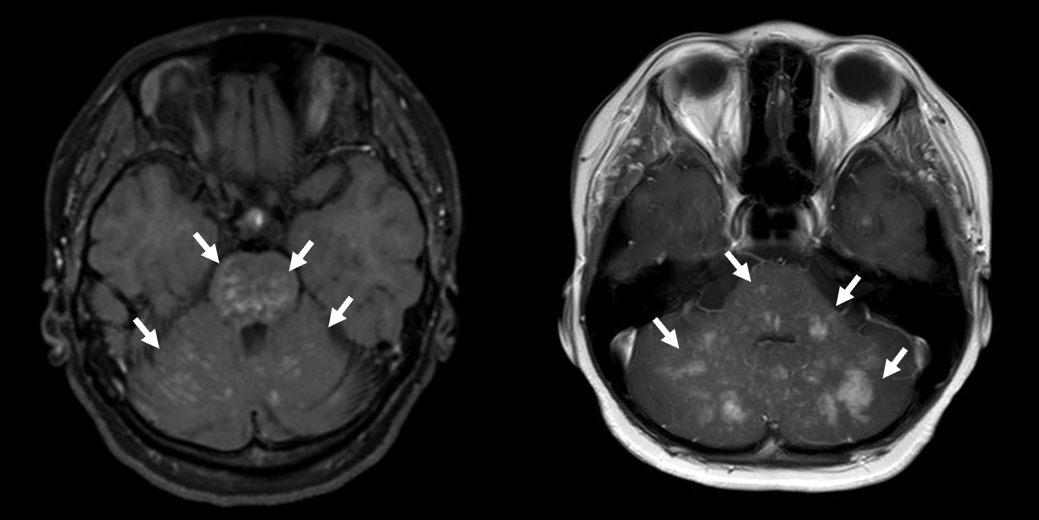

図 本研究で報告した2症例の頭部MRI(造影T1強調)画像

小脳と脳幹に、白く造影される点状・結節状の病変を多数認め(矢印)、CLIPPERSに類似する所見を示した。